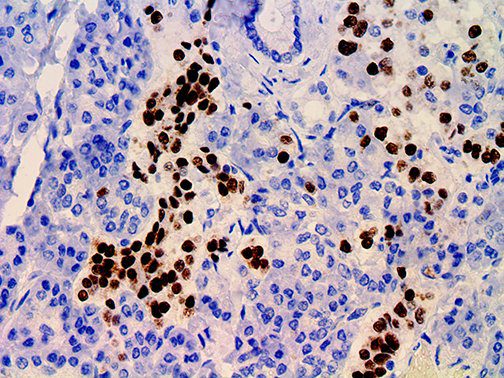

It is the ICU physician who is most likely to witness one of the deadliest manifestations of the abnormal immunological response, the cytokine storm syndrome (CSS). This response is also referred to by some as the cytokine release syndrome (CRS). CSS is characterized by continuous activation and expansion of macrophage and lymphocyte populations, which secrete large amounts of cytokines, causing the cytokine storm. This massive cytokine release is akin to hemophagocytic lymphohistiocytosis (HLH) disease, a syndrome characterized by initial unchecked and persistent activation of cytotoxic T lymphocytes and NK cells.

Clinical and laboratory manifestations of HLH include fever, enlarged liver and/or spleen, neurologic dysfunction, coagulopathy, liver dysfunction, cytopenias (i.e., low levels of erythrocytes, leukocytes, and/or platelets), hypertriglyceridemia, hyperferritinemia, hemophagocytosis, and eventually diminished NK cell activity as the immune system becomes progressively paralyzed. HLH can be familial (primary HLH) or secondary to another disease process (sHLH), such as rheumatic disease, in which it is referred to as macrophage activation syndrome (MAS, characterized by elevated ferritin).